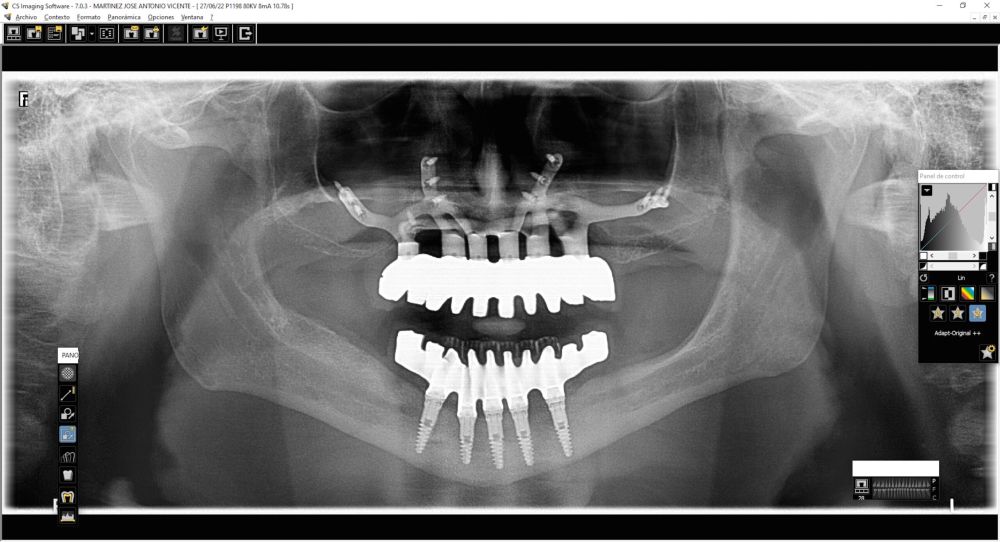

Clinical Case: A subperiosteal sintered titanium structure was fabricated with six transepithelial connections that were rehabilitated with an immediate implant supported fixed prosthesis made of PMMA. Two months later, a sintered chromium-cobalt framework with machined bases covered with acrylic resin teeth was fabricated as the final restoration. At one year follow-up, the case remains stable.